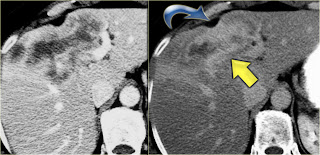

Intrahepatic cholangiocarcinoma. Capsular retraction and the late enhancement

Early and late phase enhancement of a intrahepatic cholangiocarcinomaThe key findings to look for are:

•Delayed enhancement

•Peripheral biliary dilatation

•Capsular contraction